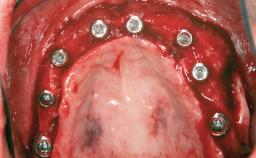

Le Fort I Interpositional Graft and Mandibular Sandwich Osteotomy for Maxillofacial Rehabilitation after Severe Periodontitis

A 47-year-old woman who had suffered from aggressive periodontitis requiring a number of periodontal interventions over more than 10 years was referred by her general dental practitioner and periodontologist for bone augmentation and implant therapy. Her failing dentition had already been scheduled for extraction. The patient expressed a desire for implant-supported fixed restorations and esthetic improvement of her lower face. She had agreed to consult with a maxillofacial surgeon after the referring dentist had suggested bone augmentation. An initial examination by the maxillofacial surgeon revealed mobility of all residual teeth in a patient who was very unhappy with the function of her removable partial dentures. Due to periodontally migrated flaring teeth and loss of occlusal support, the vertical dimension of occlusion was dramatically reduced. The patient was displeased with her lower face because of deepened nasolabial, commissural, and supramental folds.

# of Implants 14

Prosthesis Type FDP